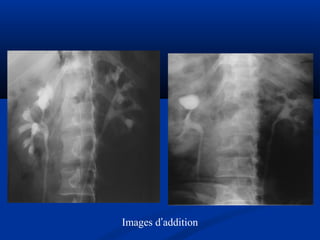

Lao niLao niệuệu

 Phân loại Elke :Phân loại Elke :

 Stade I : lao thận, X quang bình thườngStade I : lao thận, X quang bình thường

 Stade II : lao tạo hang (phá hủy < 1/3 thận)Stade II : lao tạo hang (phá hủy < 1/3 thận)

 Stade III : thận mủ > 1/3 thận (néphrectomie)Stade III : thận mủ > 1/3 thận (néphrectomie)

 UIV : khám nghiệm lựa chọn (vôi hoá, chít hẹp,UIV : khám nghiệm lựa chọn (vôi hoá, chít hẹp,

hình cộng..)hình cộng..)

Öu theá UIV trong lao nieäuÖu theá UIV trong lao nieäu

SA giuùp ích höôùng daãnSA giuùp ích höôùng daãn

Images d’addition